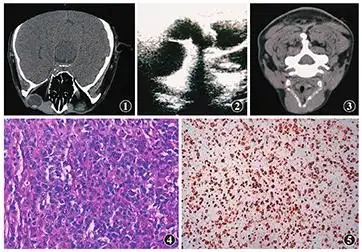

泪囊区弥漫大b细胞淋巴瘤一例